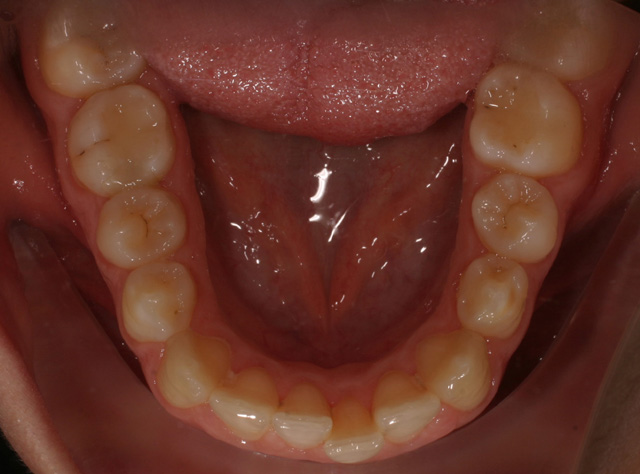

4035 visualizzazioni Trattamento eseguito con tecnica linguale 2D della RMO in un lasso di tempo molto breve, in paziente adulta con grandi esigenze estetiche.

Al fine di allineare gli elementi dentari si è ricorso allo stripping selettivo nel settore incisivo con una contenzione funale con retainer fisso; durata del trattamento da febbraio 2009 con debonding a ottobre 2009 ( 8 mesi ).